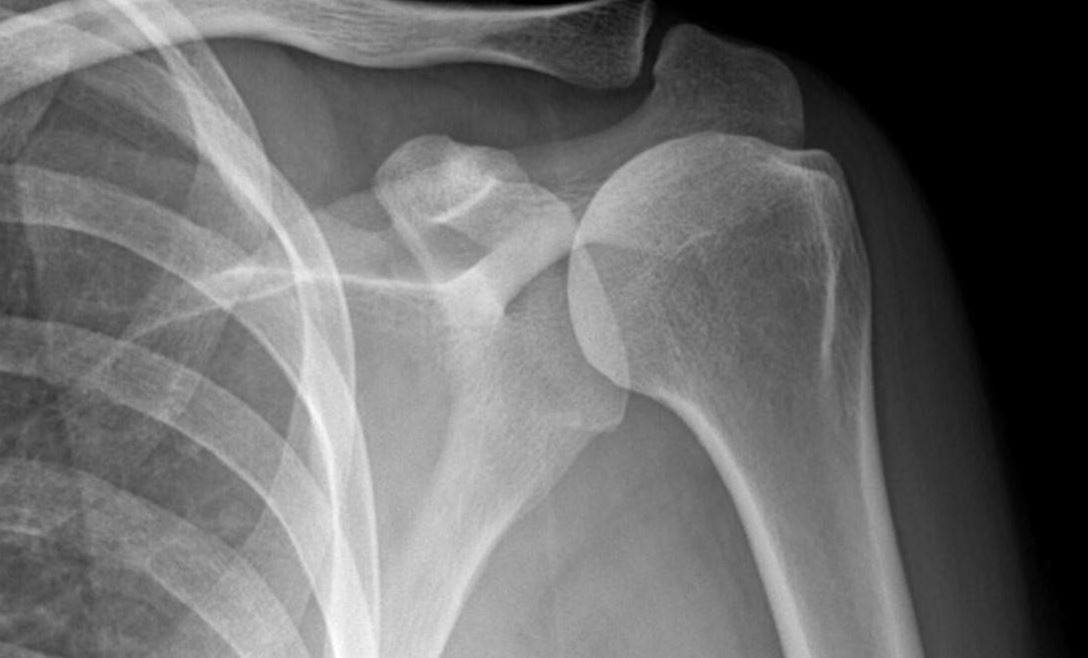

- Chụp X-quang vai: Chụp X-quang là phương pháp nhận biết các tổn thương cơ bản trong khớp vai. Một số trường hợp khi chụp X-quang có thể phát hiện hình ảnh gián tiếp của thoái hóa hay sự lắng đọng calci tại gân cơ vùng trên gai.

Có thể chẩn đoán viêm khớp vai bằng phương pháp chụp X quang